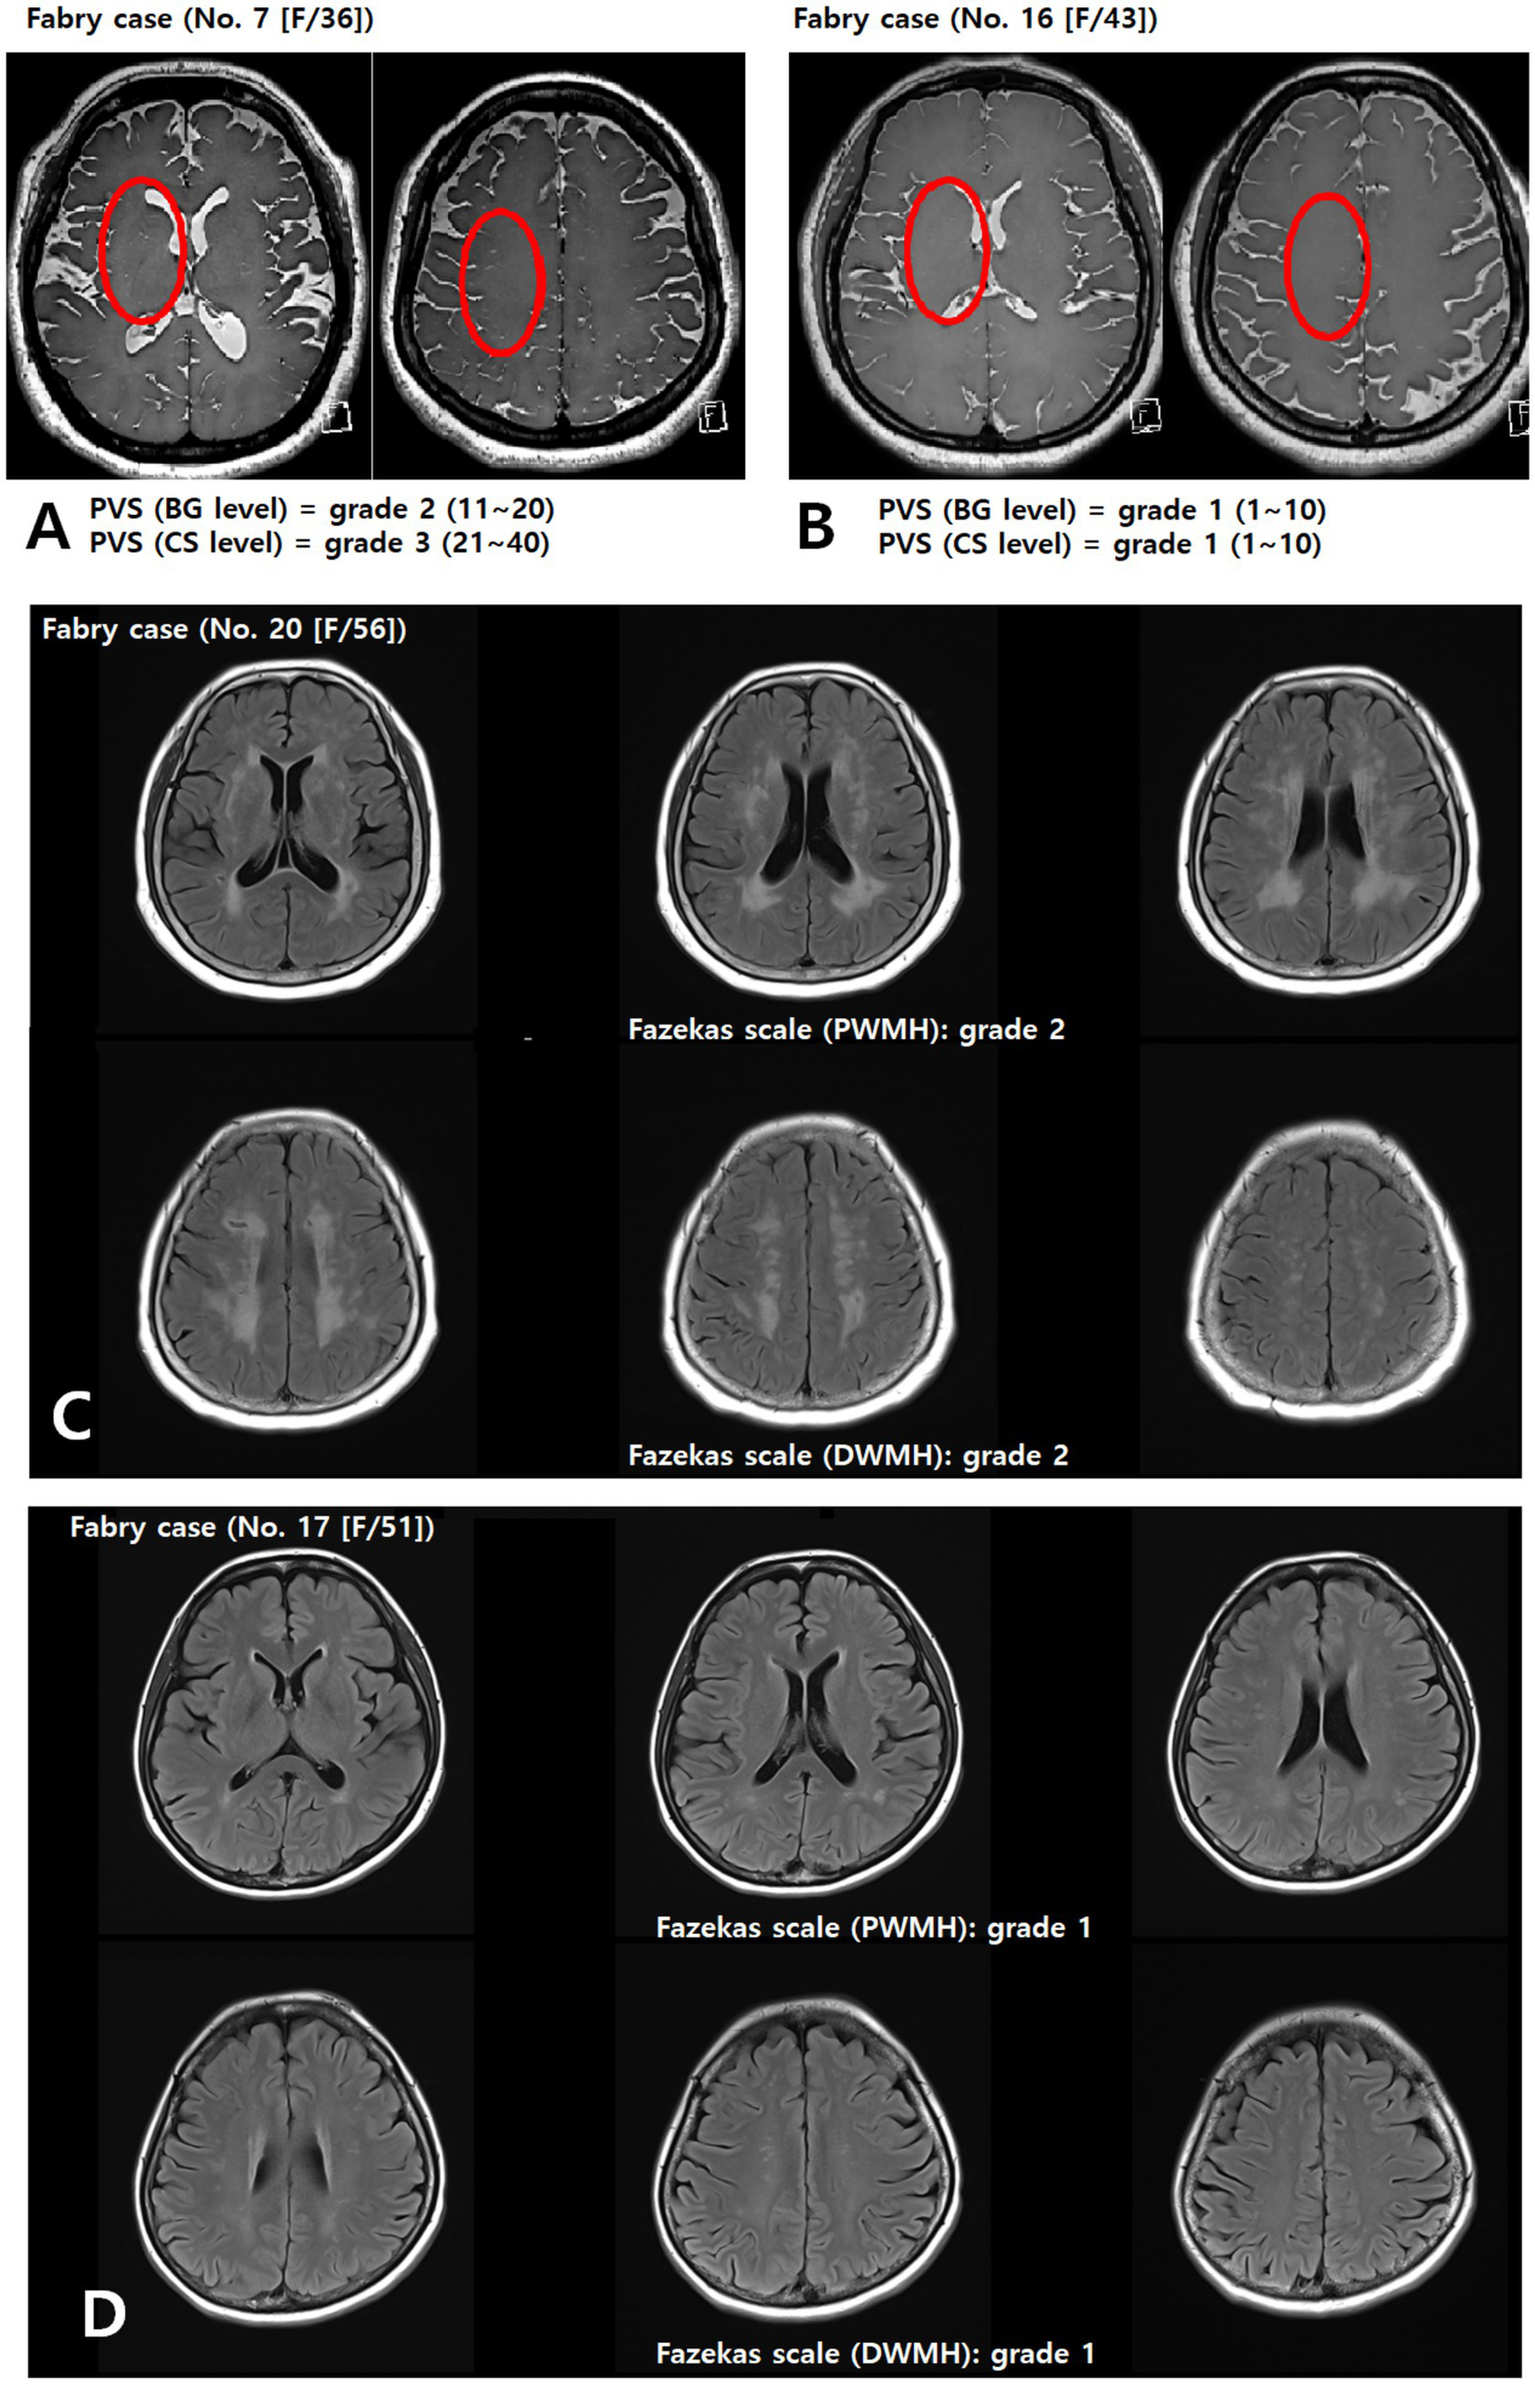

PVS appear as round, oval, or linear lacunae with well-defined edges located in areas supplied by perforating arteries. They exhibit cerebrospinal fluid-like signal intensity (hypointense on T1-weighted images, hyperintense on T2-weighted images, and isointense on FLAIR images without a hyperintense rim). Although PVS are generally <3 mm in diameter, lesions ≥3 mm can be classified as PVS if they show a typical vascular morphology along the path of the perforating arteries. We used the Standards for Reporting Vascular Changes on Neuroimaging to evaluate the number, size (maximum diameter), and location of PVS (13). Thereafter, the overall PVS burden was rated using a visual scale adapted from Potter et al. (14) separately assessing the basal ganglia (BG) and centrum semiovale (CS) on each side of the brain. The final rating was the highest score in cases of asymmetry. Scores ranged 0–4 (0 = none, 1 = 1–10, 2 = 11–20, 3 = 21–40, 4 > 40), as shown in Figures 2A,B.

Figure 2

Assessment of the PVS (A,B) and Fazekas (C,D) scales. Representative axial T2-weighted image of a patient with FD showing multiple enlarged perivascular spaces (red circle) in the basal ganglia and centrum semiovale (A). BG, basal ganglia; CS, centrum semiovale; DWMH, deep white matter hyperintensity; PVS, perivascular space; PWMH, periventricular hyperintensity.

WMLs were defined as hyperintensities on T2-weighted and FLAIR images, without cavitation. Severity was graded using a modified Fazekas scale (15), integrating periventricular hyperintensity (PWMH) and deep white matter hyperintensity (DWMH): 0 = absent; 1 = small, punctate foci (PWMH ≤ 10 mm and DWMH ≤ 10 mm); 2 = confluent or larger foci (DWMH ≤10 mm and PWMH ≥10 mm, or 10 mm ≤ DWMH < 25 mm, or DWMH ≥ 25 mm and PWMH < 10 mm); 3 = extensive confluent lesions (PWMH ≥ 10 mm and DWMH ≥ 25 mm), as shown in Figures 2C,D.